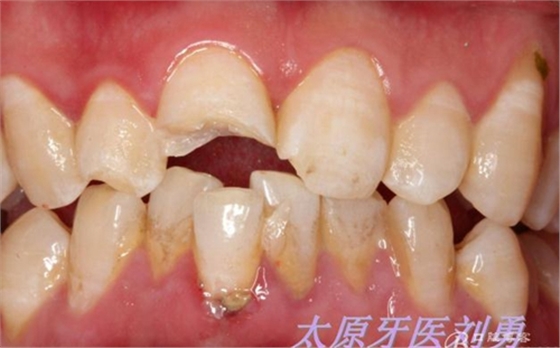

患兒8歲,不慎摔倒導(dǎo)致上前牙折斷,來(lái)院就診,行根尖片檢查,根尖孔尚未閉合,且呈喇叭口狀,就診時(shí)患兒自己帶來(lái)了折裂的牙齒碎片,口內(nèi)檢查,A1折斷1/2,斷端可見(jiàn)兩處 露髓點(diǎn),一處直徑約為1.5mm,一處約為1mm,未見(jiàn)明顯出血,B1近中切角缺損,考慮到患兒根尖孔尚未閉合,于是決定保留牙髓(若根尖孔已經(jīng)閉合,則摘除牙髓,纖維樁加強(qiáng)粘結(jié)固定折裂碎片。不多說(shuō)了,還是看術(shù)前照片:

另外一例為本人高中同學(xué),同樣不慎摔倒,導(dǎo)致A1折裂,露髓,且舌側(cè)有一碎片折裂至齦下3mm左右,先看術(shù)前圖片: